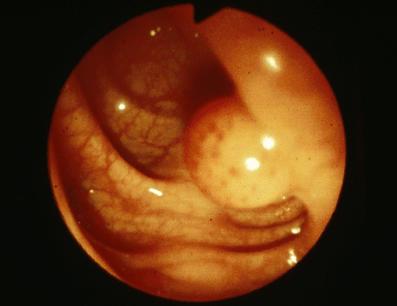

内視鏡的ポリペクトミーにて切除された、9mm大の有茎性の平滑筋腫(56歳、男)の内視鏡像

疾患(病理主体)の分類良性非上皮性腫瘍/平滑筋腫

部位(臓器別)大腸/S状

検査方法内視鏡

病変の最大径(ミリ)1〜9